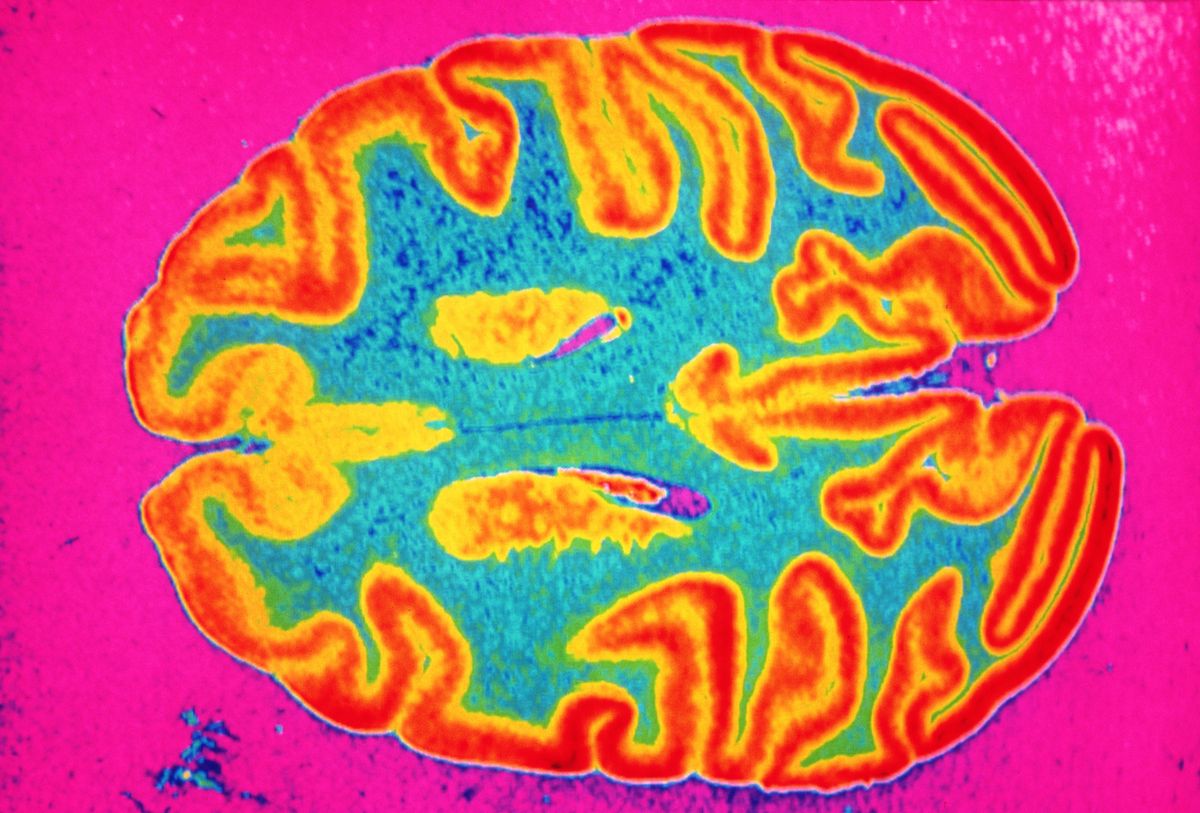

The study examined how it affected the brain(Image: Ted Horowitz Photography/Getty Images)

The US-based team were particularly eager to understand how alcohol consumption was connected to the development of Alzheimer’s disease, which is responsible for between 60% and 80% of all dementia cases. Their findings revealed that even ‘modest amounts’ of the beverage were enough to ‘accelerate brain atrophy’.

This refers to the shrinking and deterioration of brain tissue, coupled with a rise in ‘amyloid plaques’ – harmful proteins closely associated with Alzheimer’s. “These findings suggest alcohol might accelerate the pathological cascade of Alzheimer’s disease in its early stages,” said Associate Professor Shannon Macauley, of Wake Forest University School of Medicine, at the time.

Crucially, these findings aren’t just limited to mice. In 2024, scientists at Oxford University ranked alcohol among the worst offenders for weakening cognitive health and potentially worsening the risk of Alzheimer’s.

The team analysed the brain scans of 40,000 individuals to determine this. Professor Gwenaëlle Douaud, who led the study, said: “We know that a constellation of brain regions degenerates earlier in ageing, and in this new study we have shown that these specific parts of the brain are most vulnerable to diabetes, traffic-related air pollution − increasingly a major player in dementia − and alcohol, of all the common risk factors for dementia.